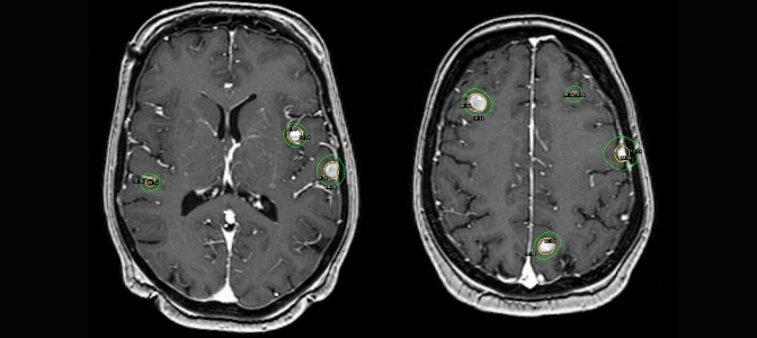

Lightning can be used to do most of the heavy-lifting, with the final ‘sculpting’ and optimization of the dose distribution being hand-crafted by the medical physicist, neurosurgeon or radiation oncologist.

The next-generation treatment optimizer

Meeting the increased demand for automated and personalized intracranial SRS

Automated planning